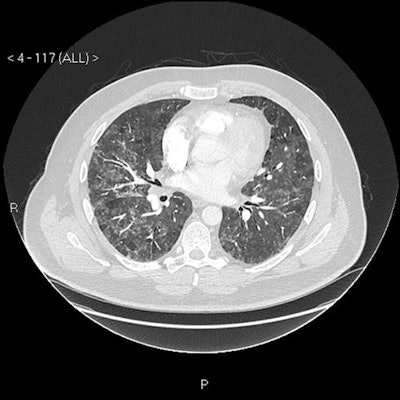

CT scan (mediastinal axial slice) with prominent reactive borderline enlarged mediastinal and hilar nodes.Blood avian precipitins were strongly positive, and lung function testing confirmed a restrictive pattern with impaired gas transfer.